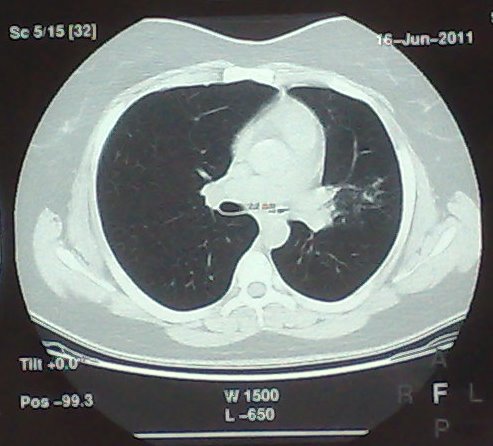

- გულმკერდის კტ სტენტირებამდე (Axial) 2 დღით ადრე

მარცხენა მთავარი ბრონქის სანათურის დიამეტრია 2.2 მმ